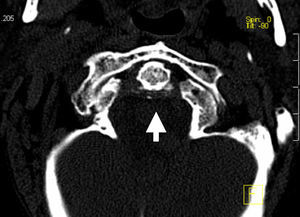

La afectación del esqueleto axial por condrocalcinosis ha estado asociada a depósitos cálcicos en disco intervertebral, ligamento amarillo, articulaciones facetarias e incluso articulaciones sacroilíacas. La calcificación del ligamento transverso del atlas (figs. 1-3) es una manifestación menos frecuente y se ha denominado síndrome de Crown Dens; constituye un cuadro clínico asintomático en la mayoría de las ocasiones, pero también puede estar asociado con brotes agudos de dolor cervical, rigidez y fiebre con las connotaciones de dificultad diagnóstica añadidas en estos casos.

En los estudios radiológicos realizados destaca la aparición de una espondiloartrosis cervical y calcificaciones en el ligamento transverso del atlas y ligamentos alares a nivel de la articulación atlo-axoidea (fig. 4).

El síndrome de Crowned Dens fue descrito por primera vez en 1985 por Bouvet et al1,2. El diagnóstico se basa en la asociación de un cuadro clínico compatible y unos hallazgos en las pruebas de imagen, fundamentalmente depósitos cálcicos en ligamentos de la articulación atlo-axoidea, visibles en la TC3,4.